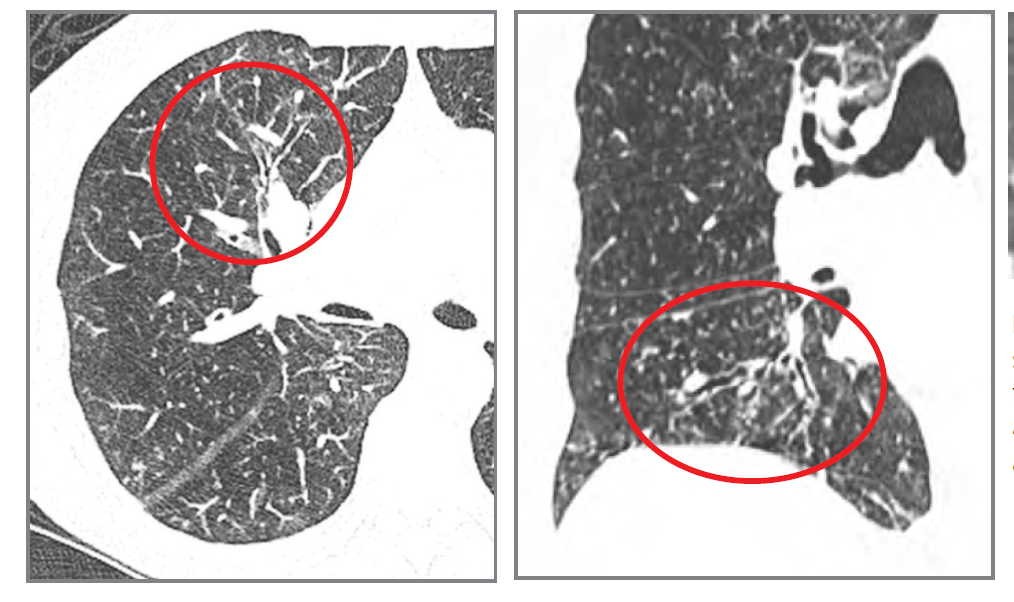

What 2 features are shown here? What condition is this?

traction bronchiectasis and string of pearls. Varicose bronchectasis.

What 2 features are seen here?

honeycombing and traction bronchiectasis